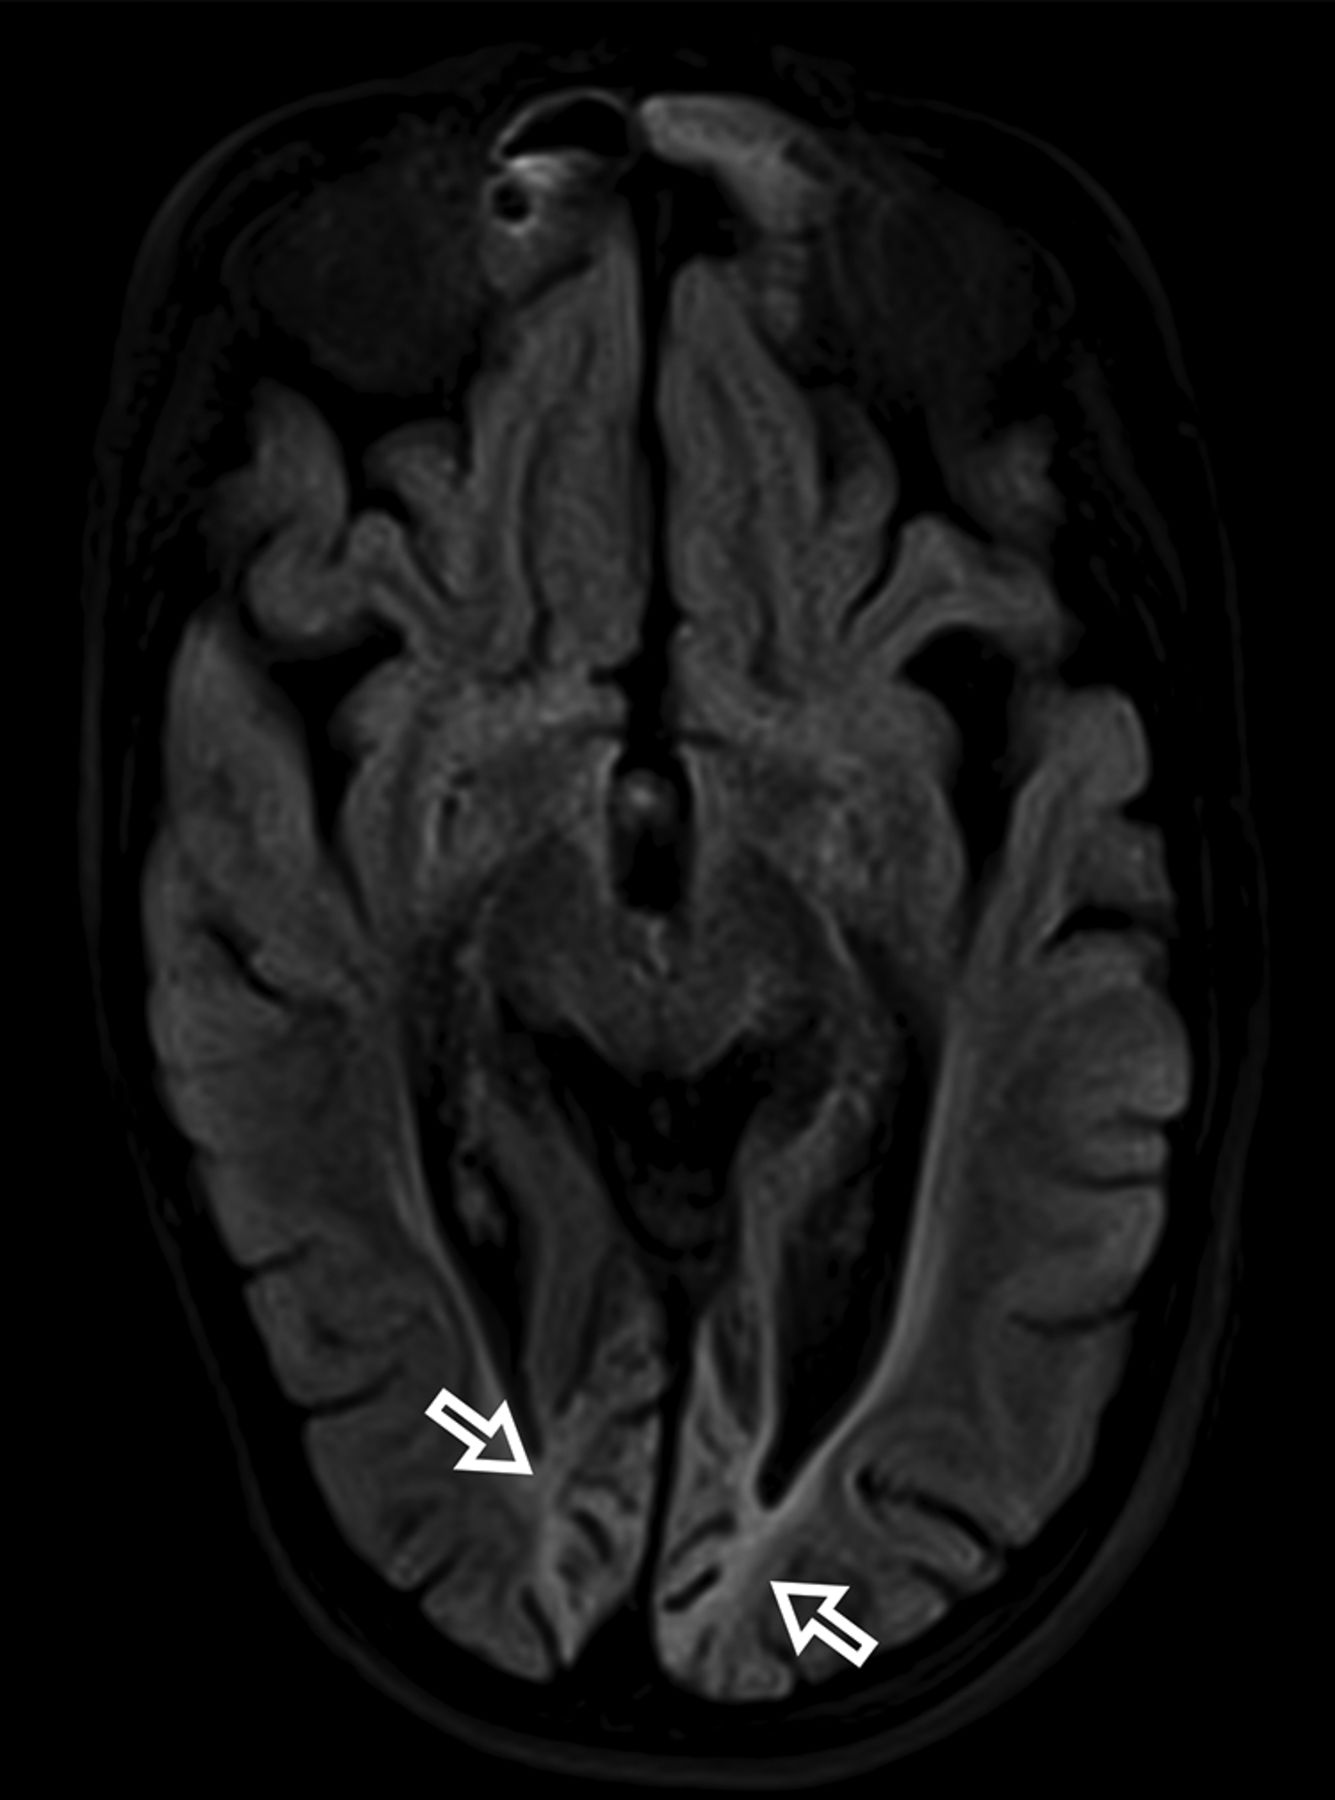

All patients had at least 1 follow-up brain MR imaging. Most patients had imaging findings suggesting disease progression (n = 12, 92%) or a fatal outcome. On follow-up imaging, most demonstrated volume loss (n = 10, 77%), which was typically very rapid, in a matter of a few weeks in most patients. On the follow-up brain MR imaging, the perirolandic and thalamic signal changes had various evolutions, with resolution, stability, contralateral involvement (unilateral → bilateral), or progression with time. The most affected brain regions at follow-up were the occipital lobe (n = 8, 61%) and thalamus (n = 8, 61%). The perirolandic sign was detected in 3 patients who did not have any evidence of perirolandic involvement at diagnosis. Other affected brain regions included the hippocampus, brain stem, dentate nucleus, cerebellar vermis, cerebellar hemispheres, other regions of the frontal and parietal lobes, and the occipital (Fig 4) and temporal lobes. ASL perfusion was obtained in only some of the patients at follow-up imaging. Regions more commonly found with increased ASL perfusion included the thalamus, the perirolandic region, and the occipital and parietal lobes. The areas with increased ASL perfusion also had signal changes visible on T2WI, FLAIR, or DWI. An increased lactate peak was seen in all patients in whom MR spectroscopy was performed on follow-up. Diffuse brain edema was noted in 1 patient, who died shortly thereafter. One patient had unremarkable brain MR imaging on follow-up with resolution of findings.

Bilateral occipital volume loss, gliosis, and encephalomalacia in a 16-year-old female patient with POLG-related disorder (open arrows).

Volume loss was detected almost always on follow-up imaging. Volume loss varied from mild to severe, showing rapid evolution in most cases. Most important, volume loss showed no lobar predominance in most patients. However, in severe cases, the occipital lobes were affected asymmetrically and with encephalomalacic changes. Signal changes were detected virtually in any part of the brain, except the medulla. The spinal cord was not part of the scope of this study.